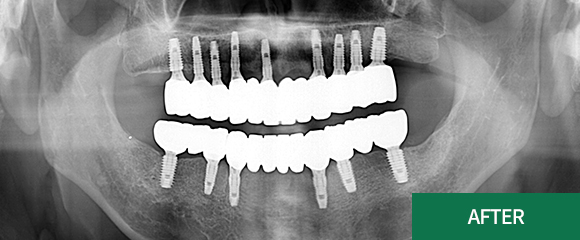

전악(전체) 임플란트